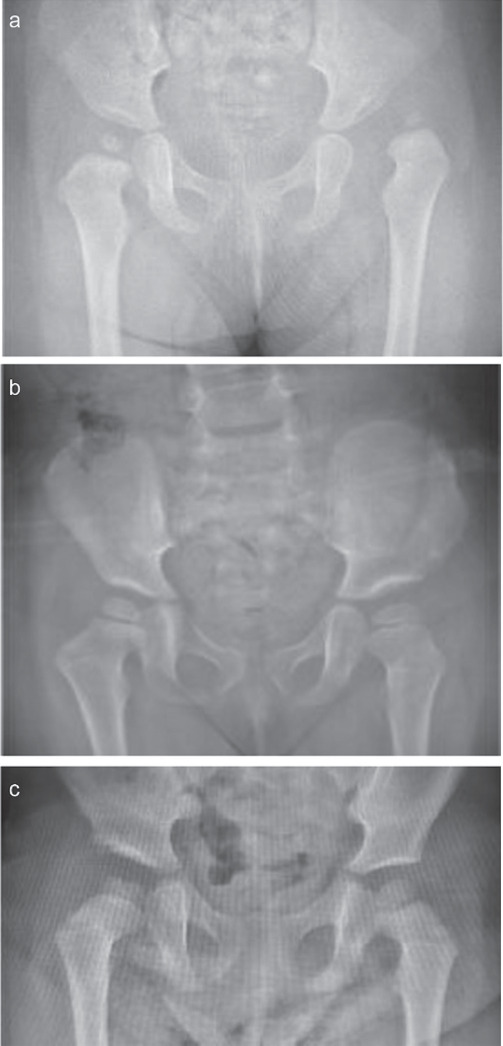

目的本研究旨在探讨Salter和Pemberton骨盆截骨术与股骨头缺血性坏死在治疗发育性髋关节发育不良(DDH)中是否存在关系。方法本回顾性研究包括52名年龄在12-36个月之间的患者中的69个髋关节,这些患者被诊断为DDH,并接受了Salter或Pemberton骨盆截骨,采用Smith-Petersen方法。Salter骨盆截骨术组35例,Pemberton骨盆截骨组34例。DDH治疗前采用Tönnis分类法,测量术前和术后24个月髋臼指数(AI)角度。根据股骨头缺血性坏死的存在来确定Kalamchi MacEwen级别的缺血性坏死。结果在中期随访结束时,两个截骨组在放射学参数和股骨头缺血性坏死方面没有显著差异。然而,研究发现,缺血性坏死发生率的增加与Tönnis 4级髋关节显著相关。结论Salter和Pemberton截骨术对股骨头的影响都可以安全地用于DDH的治疗。证据水平III级,治疗研究。

Methods: This retrospective study included 69 hips of 52 patients aged between 12-36 months, diagnosed as DDH who had undergone either Salter or Pemberton pelvic osteotomy with Smith Petersen approach. There were 35 patients in Salter Pelvic Osteotomy and 34 patients in Pemberton Pelvic Osteotomy groups. Before the treatment of DDH, Tönnis classification was used, preoperative and 24th month postoperative Acetabular Index (AI) angles were measured. Kalamchi-MacEwen grades of avascular necrosis were determined in terms of presence of avascular necrosis of the femoral head.

Results: There were no significant differences between two osteotomy groups at the end of mid-term follow up in terms of the radiological parameters and avascular necrosis of femoral head. However it was found that the increased avascular necrosis incidence was significantly associated with Tönnis grade 4 hips.